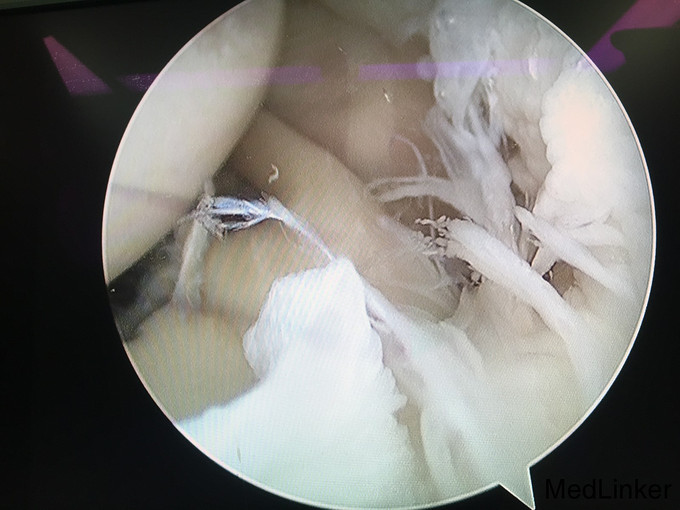

1、诊断:左肩创伤性前不稳定,左肩SLAP损伤。 2、治疗:全麻下行左肩关节镜下前盂唇、上盂唇修补术。

随访:患者术后前臂吊带悬吊5周,期间左肩被动活动。术后第6周开始左肩全方向的活动度练习及肌力练习。术后3月完全恢复左肩活动度。术后半年恢复左肩运动。 讨论:肩关节前不稳定或SLAP损伤患者,疼痛不是主要症状,关节弹响、不稳定感是主要症状。应及时前往运动医学关节外科就诊,并及时接受手术治疗。